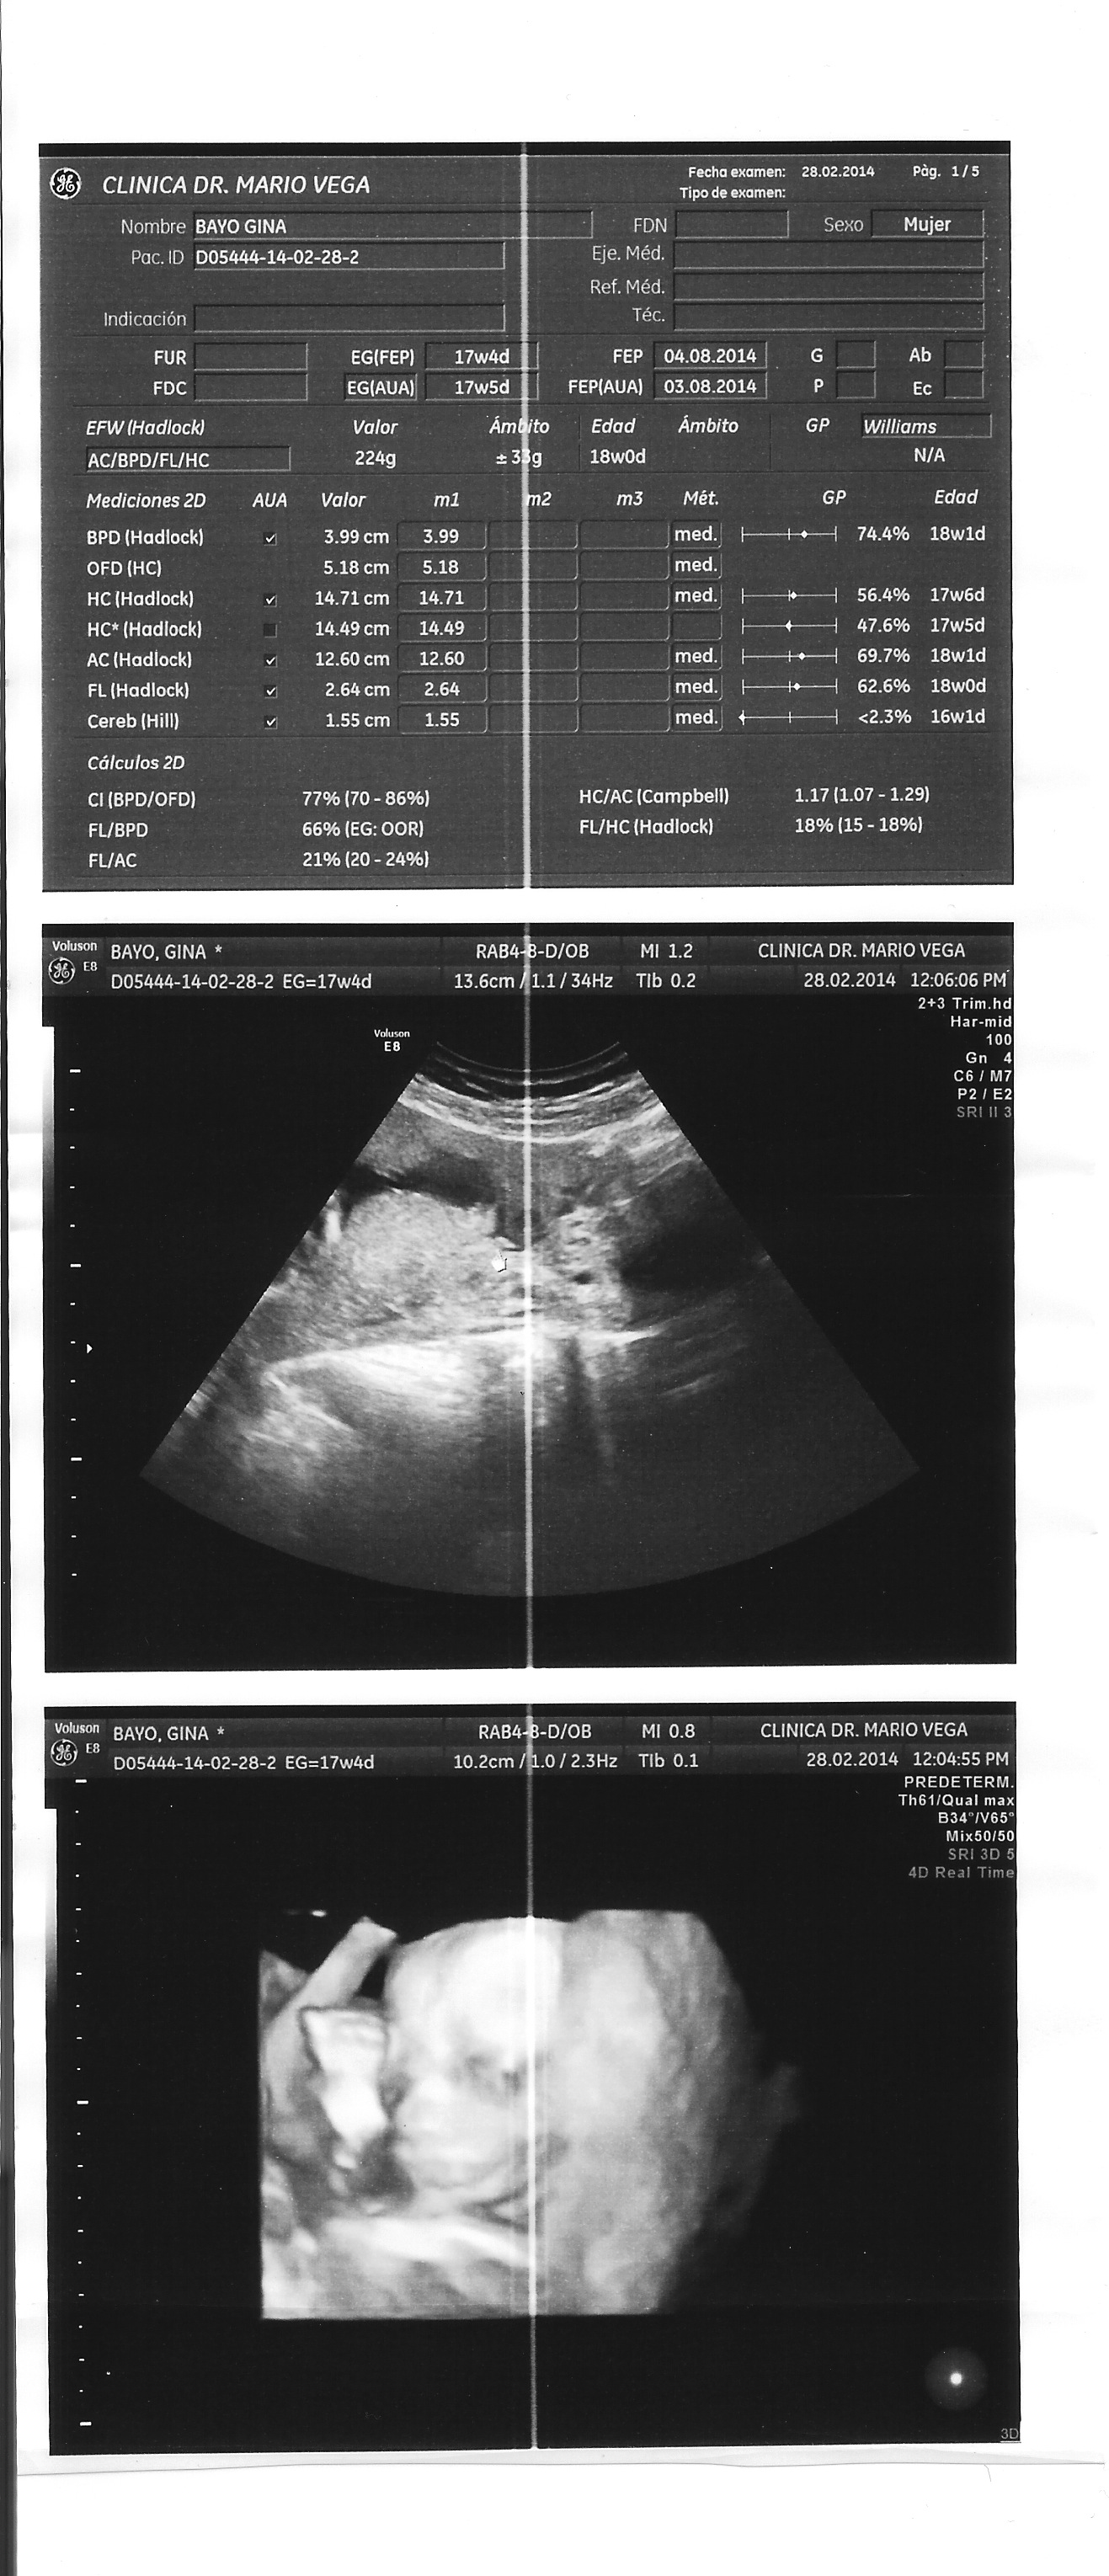

Ya la cuarta cita fue con 3D y todo, las demás tomas fueron de partes del cuerpo, para medir los huesos de las piernas, la cabeza, el estómago. En esta cita sorprendentemente tuve que esperar menos. Debe ser que era viernes antes de carnaval. La placenta sigue baja, pero por lo demás todo muy bien.